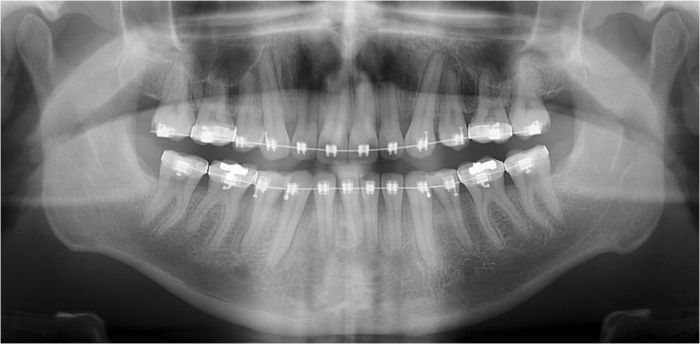

Mordida inicial